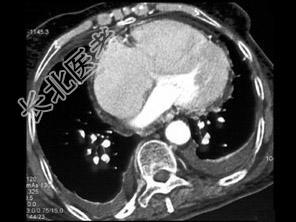

- 单项选择题男,38岁, 反复咳嗽、咳痰伴发热15年余,痰结核菌素试验(—), 结合CT图像,最可能的诊断是 ( )